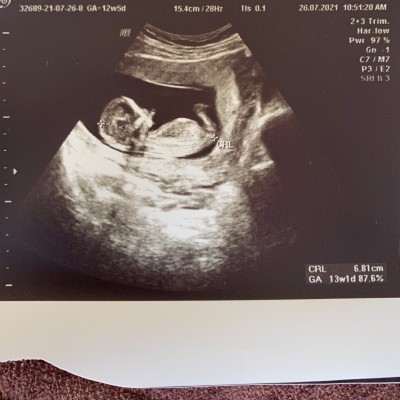

Merhaba 13 haftalık hamileyim doktorum bir tahmin de bulunmadı. Yakın zaman da cinsiyeti öğrenirim kız veya erkekte farketmiyor sağlıklı olsun yeter ama yine de merak işte :) Nub teorisinden anlayanlar oluyormuş ben bilmediğim için sizlere sormak istedim :) Bebeğimin cinsiyeti için bir tahmin de bulunur musunuz ?

image

Alın be burun arasında çıkıntı görünüyorsa ve popo yukarı bakıyorsa erkek diyorlr ben onların yalancısıyim :D

Hayırlısı artık ilk kızımla benziyor bu hafta ki ultrason görüntüsü o yüzden net anlayamadım ben 2 hafta sonra öğrenirim inşallah  :)

Kıza benziyor